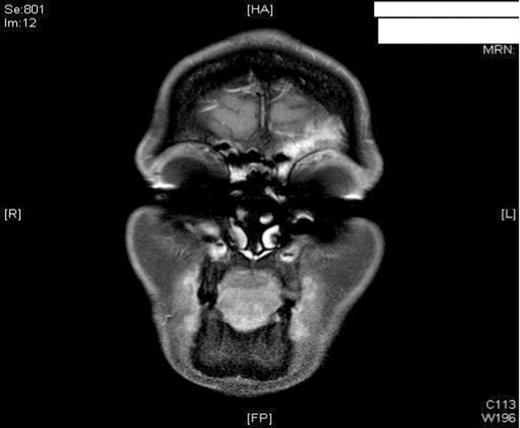

A 47-year old female smoker presented to the ENT department with worsening pain and progressive swelling to her left peri-orbital region and eyelid. On clinical examination the patient was acutely unwell. Rhinoscopy revealed mucopus draining from the left middle meatus. CT scanning revealed severe sinus disease in both frontal sinuses, with the left frontal sinus being expanded suggesting the presence of a mucocele (Figure 1). Both Frontonasal recesses and osteomeatal complexes were seen to be occupied by material bilaterally. Following Opthalmological review, she was managed initially with intravenous antibiotics and systemic steroids as well as intranasal steroids, decongestants and antimicrobial eye ointment. However, due to failure in resolution of symptoms, she was listed for surgical drainage of the mucocele using balloon sinuplasty.

MRI imaging (a) coronal (b) axial views post procedure revealing resolution of the mucocele and no intracranial or orbital complications (see figure 1).